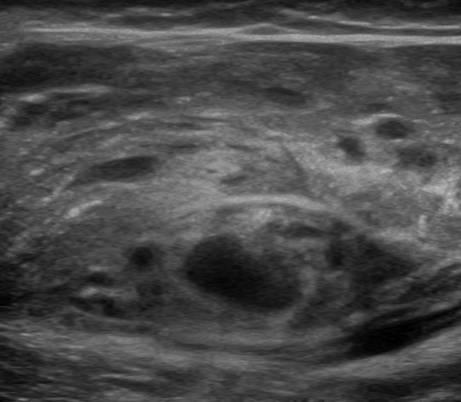

U xơ cơ

» Thông tin: Nữ giới – 3 tháng tuổi.

» Lâm sàng: Sưng vùng đùi.